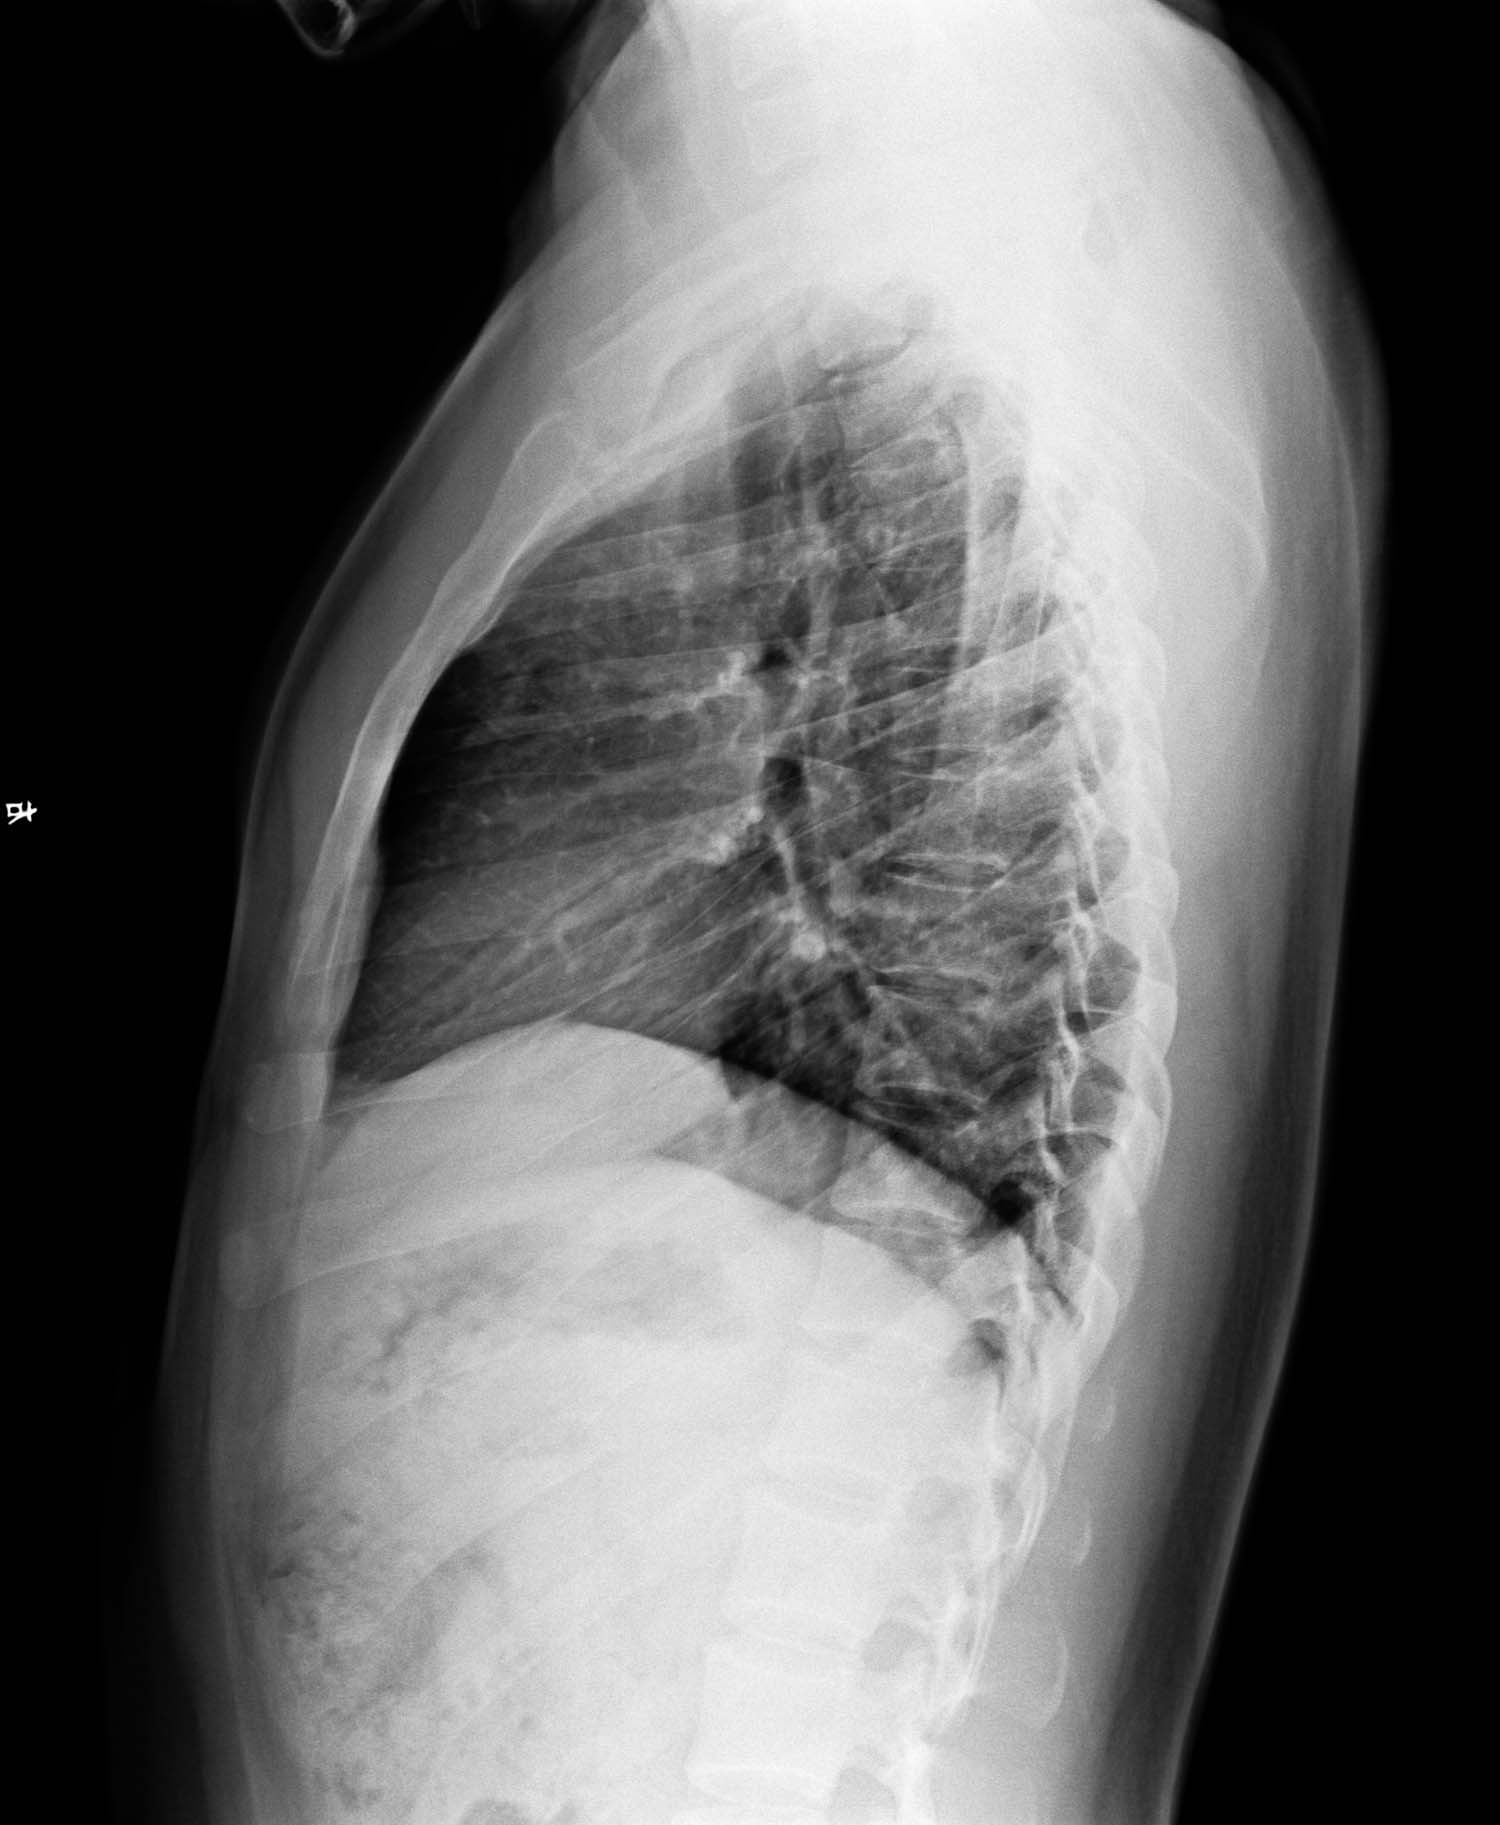

侧位片未见明显异常,右肺门旁影暂考虑右6后肋,右2前肋前端,局部肺纹理及右上肺动脉所至重叠影,必要时ct检查排除其它。另双肺纹理稍多,考虑支气管疾患,不知有否类似症状?

正位示右肺门类圆形肿块影,侧位未见显示,建议ct进一步检查.

结合年龄考虑:原发型肺结核可能,还是做个ct更精确,毕竟恻位片上没见到。

有肺门处阴影,侧位未见其影。考虑血管影